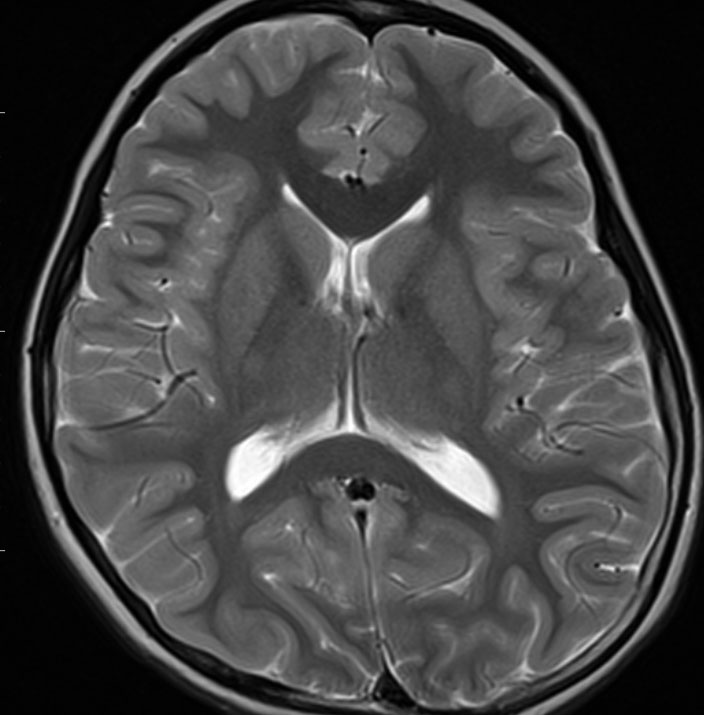

3歳時に28.8グレイの頭蓋照射を受けた子の大脳全般の萎縮性変化です。播種があった例なのでこの放射線治療は救命のためには必要なものでした。